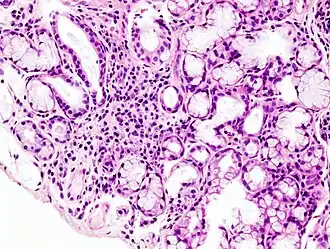

S'il n'existe pas d'anticorps anti-SSA ou anti-SSB dans le sérum, le diagnostic de certitude est apporté par l'analyse anatomo-pathologique d'une biopsie des glandes salivaires accessoires.

Un score est utilisé pour définir le syndrome de Sjögren primitif, basé sur les tests ophtalmologiques, la biopsie des glandes salivaires, la présence d'anticorps anti SSA et la mesure du débit salivaire[13].